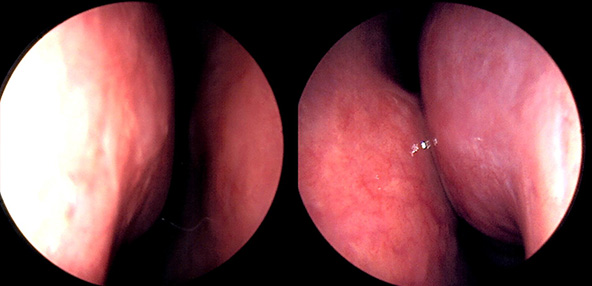

※ 비중격 비염 수술 후 생길 수 있는 부작용으로는 출혈, 감염, 염증이 있을 수 있습니다.

본 사진은 의료기관에서 진료를 본 환자이고, 전후 사진 인물이 동일인이며,동일조건에서 촬영이 되었습니다.